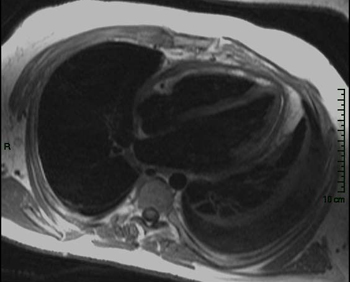

19) What abnormality is seen on the sagital view below?